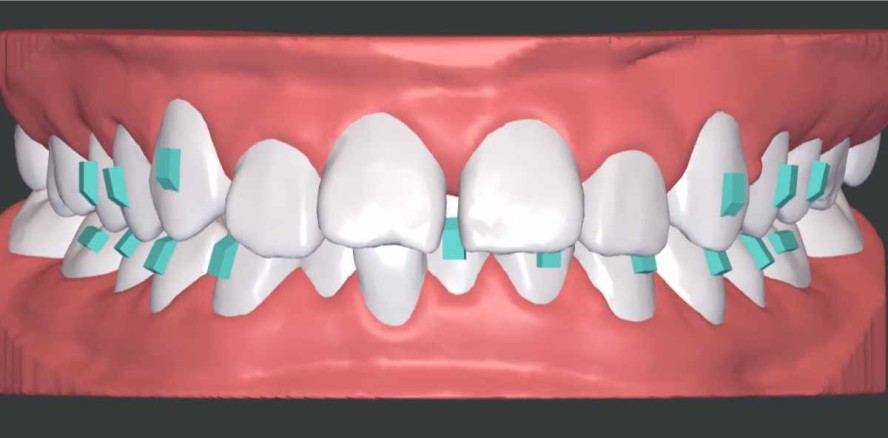

Die Einstellung in eine Klasse I-Verzahnung wurde außerdem durch eine umfangreiche Distalisation der Oberkieferseitenzähne und geringere Distalisation der Unterkieferseitenzähne geplant. Trotz hoher Trimline mit einer erhöhten Retention erfolgte eine rein sequenzielle Distalisation (Abb. 4), um einem Verankerungsverlust vorzubeugen.1,2 Zusätzlich wurde die Oberkiefermolarenbewegung mit einem Tipback und einer Mesial-out-Rotation kombiniert, um eine korrekte Achsenstellung und Kontaktpunktsituation zu erreichen. Gleichzeitig entspricht diese Art der Bewegung der natürlichen Zahnbewegung und ist somit besonders verankerungsschonend.

Attachmentplanung

Im Unterkiefer wurden auf den Eckzähnen und Prämolaren vertikale rechteckige Attachments geplant, um die Vorhersagbarkeit der Frontzahnintrusion zu erhöhen. Die horizontalen rechteckigen Attachments auf den ersten Unterkiefermolaren dienten als Ausgleich für die durch Klasse II-Gummizüge erzeugten Abzugskräfte. Im Oberkiefer wurden analog auf den Eckzähnen und Prämolaren vertikale rechteckige Attachments geplant, um die Oberkiefer-Frontzahnintrusion zu gewährleisten (Abb. 5a–c).